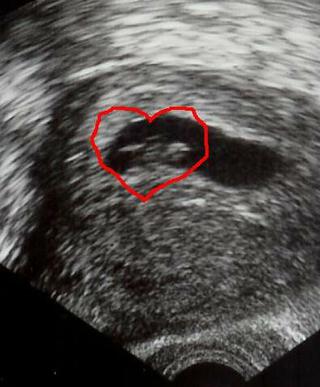

Inak srdiecko sa tvori uz v 5tt, v 6tt zacina bit, ale je take malilinke, ze to na beznom sone tazko lekari vedia potvrdit. A aj lekari maju rozne kvalitne sona. Ale od 7tt uz ich zacina vacsina lekarov vidiet ... 😉

Nasa fazulka vyzerala takto... 🙂